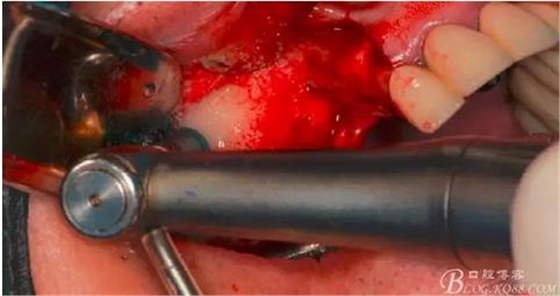

此時(shí)頰側(cè)竇膜與骨壁已經(jīng)分離,無需擔(dān)心開窗損傷竇膜。使用環(huán)切鉆以小洞口為中心開窗,轉(zhuǎn)速500轉(zhuǎn),為了保證安全,可以將種植機(jī)調(diào)成反轉(zhuǎn)模式,一樣有強(qiáng)大的切割效率。

因缺牙多,需要植骨的區(qū)域大,在遠(yuǎn)中再環(huán)切一窗口。

使用窗口擴(kuò)大鉆,這也是這套工具盒里一個(gè)亮點(diǎn),其前端是圓形高度光滑的,鉆體是有側(cè)切功能的。工作時(shí)用光滑的圓頭頂開已經(jīng)剝離的竇膜,用鉆體部分將窗口周邊不規(guī)則的部分磨掉,同時(shí)可以擴(kuò)大窗口。